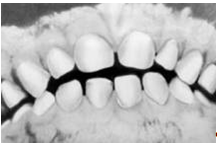

Рис. 8. Последовательность прорезывания молочных зубов у грудного ребенка (схематическое изображение): а — нижние центральные резцы (появляются примерно в 6-7 мес.), б — верхние центральные резцы (появляются в 7-8 мес.), в — верхние боковые резцы (появляются в 8-10 мес.), г — нижние боковые резцы (появляются в 10-12 мес.). 5. Классификация некариозных поражений зубов Разнообразие этиологических факторов, вариации клинических проявлений в некоторой степени препятствуют созданию всеобъемлющей клинической классификацией некариозных поражений зубов. Многообразные некариозные поражения зубов соответственно времени их возникновения следует подразделять на две основные группы: 1. Поражения зубов, возникающие в период фолликулярного развития их тканей, т. е. до прорезывания зубов: а) гипоплазия эмали; б) гиперплазия эмали; в) эндемический флюороз зубов; а) аномалии развития и прорезывания зубов, изменения их цвета; д) наследственные нарушения развития зубов. 2 Поражения зубов, возникающие после их прорезывания: а) пигментации зубов и налеты; б) стирание твердых тканей; в) клиновидный дефект; г) эрозия зубов; д) некроз твердых тканей зубов; е) травма зубов; ж) гиперестезия зубов. 6. Поражения зубов, возникающие в период фолликулярного развития их тканей 1)ГИПОПЛАЗИЯ ЭМАЛИ Гипоплазия эмали расценивается как порок ее развития, наступающий в результате нарушения метаболических процессов в развивающихся зубах и проявляющийся в количественном и качественном нарушении эмали зубов. Некоторые исследователи считают, что при гипоплазии нарушается формирование зубных тканей за счет изменения в образующих эмаль клетках — энамелобластах. Другие авторы рассматривают гипоплазию эмали как дефект ее минерализации при нормальном формировании зубных тканей. Указывается на невозможность разделения этих двух взаимосвязанных процессов. По их мнению, гипоплазия твердых тканей зуба возникает в результате нарушения как формирования эмали энамелобластами, так и ослабления процесса минерализации эмалевых призм. Считается, что при гипоплазии нарушены не только процессы минерализации, но в первую очередь построение белковой матрицы эмали зуба в результате недостаточной или' замедленной функции энамелобластов. Гипоплазия тканей зуба возникает при нарушении метаболических процессов в зачатках зубов под влиянием нарушения минерального и белкового обмена в организме плода или ребенка (системная гипоплазия) или местно-действующей на зачаток зуба причины (местная гипоплазия). При гибели энамелобластов эмаль не образуется. Недоразвитие эмали при гипоплазии необратимо, т. е. гипопластические дефекты не претерпевают обратного развития и остаются на эмали зубов на весь период жизни. Классификацию гипоплазии эмали следует основывать на этиологическом признаке, так как гипоплазия зубных тканей различной этиологии имеет специфику, которая выявляется при клинико-рентгенологическом исследовании. В зависимости от причины возникает гипоплазия твердых тканей группы зубов, формирующихся в один и тот же промежуток времени (системная гипоплазия), или нескольких рядом стоящих зубов одного, а чаще разного периода развития (очаговая одонтодисплазия). Наблюдается и гипоплазия одиночного зуба (местная гипоплазия). Очаговая одонтодисплазия описана в специальной литературе под разными названиями: фантомные зубы, незавершенный одонтогенез, одонтодисплазия. Это редкая патология, встречающаяся у практически здоровых детей.. Характеризуется запоздалым развитием и прорезыванием нескольких рядом расположенных зубов, как временных, так и сменяющих их постоянных, одного или разного периода развития. Чаще страдают резцы, клыки или постоянные моляры, реже — все зубы одной половины верхней челюсти. Коронки этих зубов уменьшены за счет недоразвития эмали, имеют желтоватую окраску и шероховатую поверхность. На рентгеновских снимках твердые ткани представляются истонченными по сравнению с зубами противоположной стороны этой же челюсти, с укороченными корнями и более широкими каналами и неодинаковой плотностью тканей в различных участках коронок, что говорит о нарушенной минерализации. Этиология этой патологии не установлена. Дифференцировать этот вид гипоплазии следует от системной и местной гипоплазии, а также наследственного нарушения развития эмали. Системная гипоплазия тканей зуба характеризуется нарушением строения эмали всех или только той группы зубов, которая формируется в один и тот же промежуток времени. По данным разных авторов, эта форма встречается у 2—14% детей. Возникает она в результате глубокого расстройства процессов ассимиляции и диссимиляции в организме плода под влиянием нарушенного обмена у беременной женщины или в организме ребенка под влиянием перенесенных заболевании или нарушения питания. К системной гипоплазии могут также приводить некоторые лекарственные вещества (тетрациклины), принимаемые будущей матерью во второй половине беременности или вводимые в организм ребенка.' По материалам обследования детей г. Казани в 1992 г., системная гипоплазия зубов в возрасте от 2 до 13 лет наблюдается при молочном прикусе у 13%, а при сменном—у 7,4% детей. Системная гипоплазия эмали постоянных зубов отмечается у 1,9% практически здоровых детей. У детей, страдавших хроническими соматическими заболеваниями, сопровождающимися расстройством обмена веществ (начавшимися до или вскоре после рождения), гипоплазия зубов наблюдается значительно чаще (50% случаев и более).